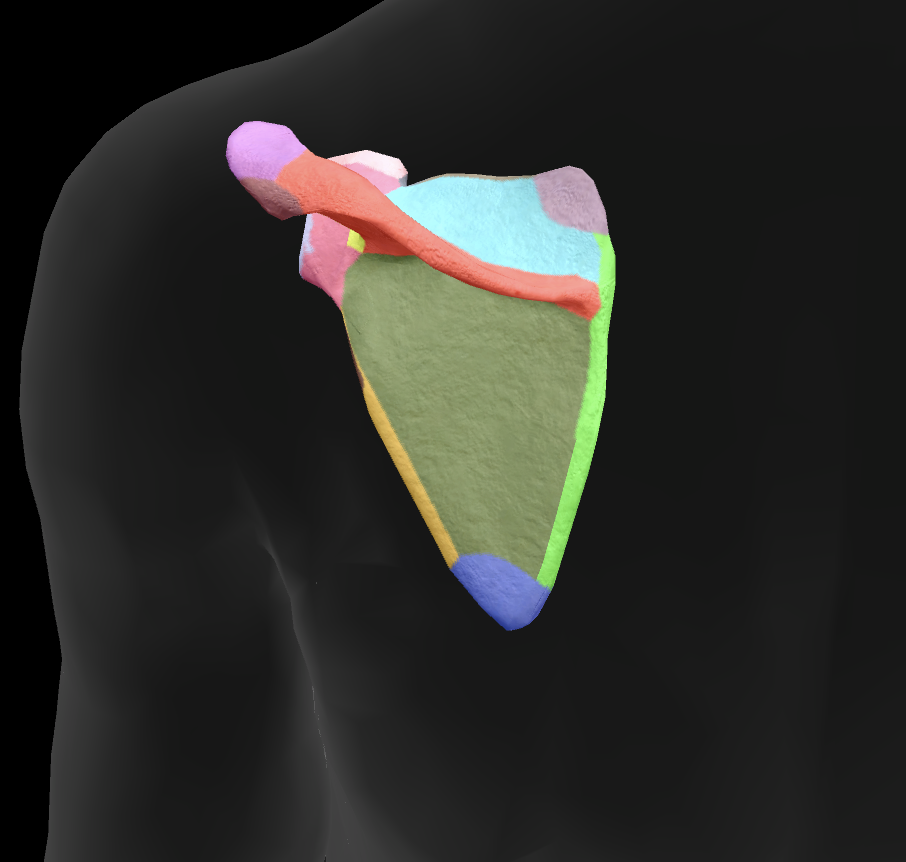

scapula

What is this boney landmark?

spine of scapula

What is this boney landmark?

supraspinous fossa

What is this boney landmark?

infraspinous fossa

What is this boney landmark?

acromion process

What is this boney landmark?

superior angle

What is this boney landmark?

inferior angle

What is this boney landmark?

lateral border

What is this boney landmark?

medial border

What is this boney landmark?

subscapular fossa

What is this boney landmark?

spinoglenoid notch

What is this boney landmark?

glenoid fossa

What is this boney landmark?

supraglenoid tubercle

What is this boney landmark?

infraglenoid tubercle

What is this boney landmark?

coracoid process

What muscle is this?

subscapularis

What muscle is this?

supraspinatus

What muscle is this?

infraspinatus

What muscle is this?

teres minor

What are the rotator cuff muscles?

supraspinatus, infraspinatus, teres minor, subscapularis